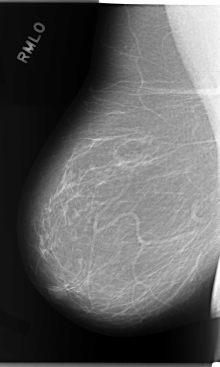

C_0114_1.RIGHT_MLO

RIGHT_MLO LINES 5864 PIXELS_PER_LINE 3512 BITS_PER_PIXEL 12 RESOLUTION 50 NON_OVERLAY